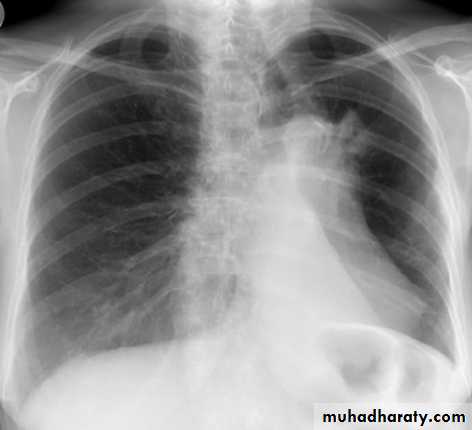

Left lower lobe collapse has distinctive features, and can be readily identified on frontal chest radiographs, provided attention is paid to the normal cardiomediastinal contours. The shadow cast by the heart does however make it harder to see than the right lower lobe collapse

Radiographic features

Left lower lobe collapseis readily identified in a well penetrated film of a patient with normal sized heart, but can be challenging in the typical patient with collapse, namely unwell patients, with portable (AP) often under-penetrated films, often with concomitant cardiomegaly. Features to be observed include :

triangular opacity in the posteromedial aspect of the left lung

edge of collapsed lung may create a 'double cardiac contour'

left hilum will be depressed

loss of the normal left hemidaphgragmatic outline

loss of the outline of the descending aorta

Non-specific signs indicating left sided atelectasis are usually also be present including:

elevation of the hemidiaphragm

crowding of the left sided ribs

shift of the mediastinum to the left

On lateral projection the left hemidiaphragmatic outline is lost posteriorly and the lower thoracic vertebrae appear denser than normal (they are usually more radiolucent than the upper vertebrae) .